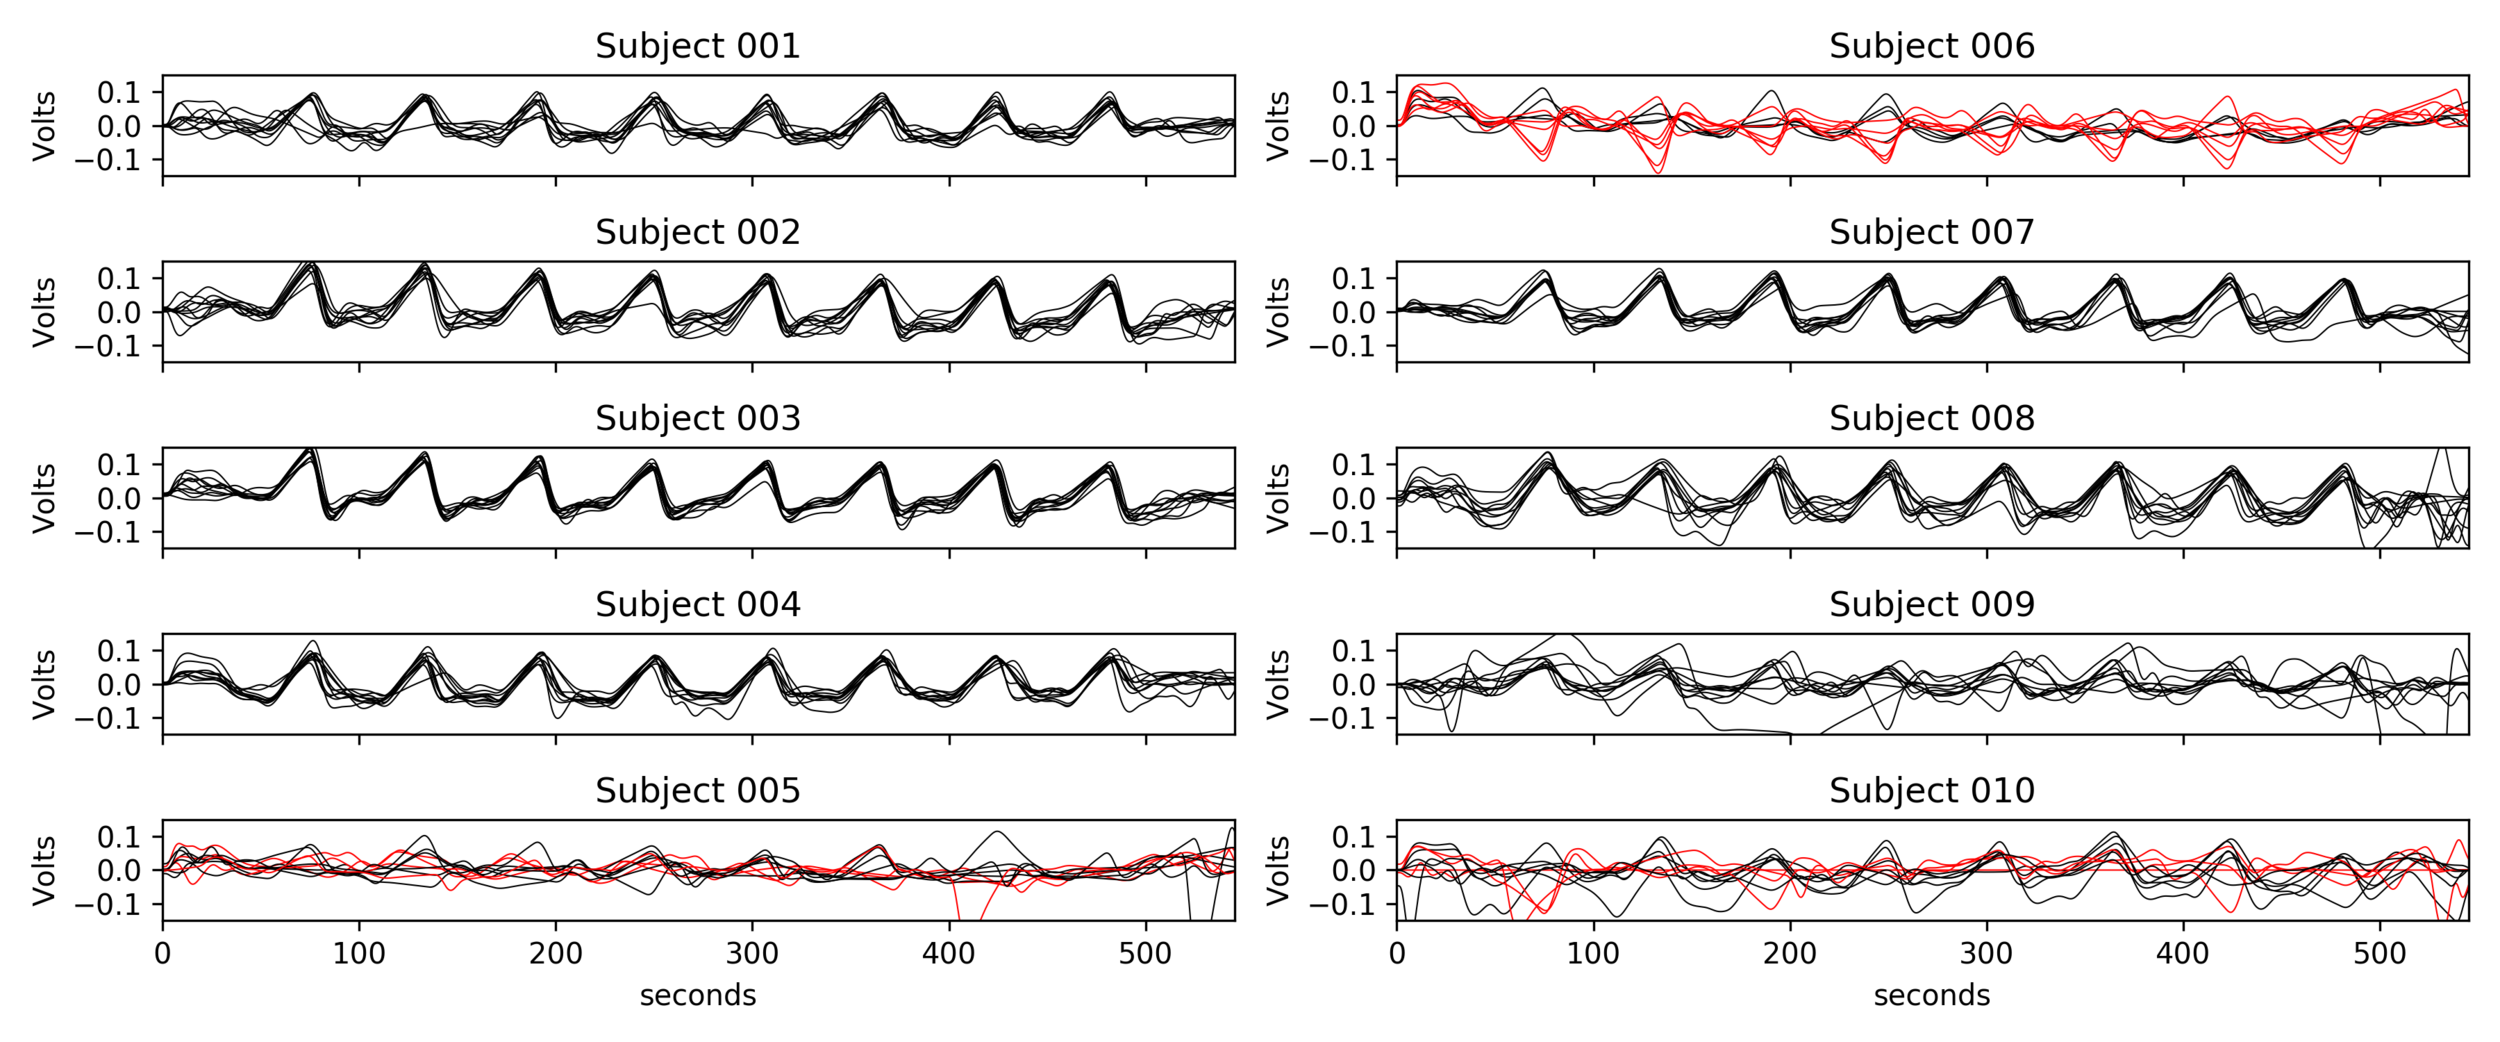

EuskalIBUR

* TR = 1.5 s, TEs = 10.6/28.69/46.78/64.87/82.96 ms, MB acceleration factor = 4, GRAPPA = 2, voxel size = 2.4x2.4x3 mm³

10 neurotypical subjects

(5F, age 25-40y)

10 sessions, one week apart, same time of the day

BH paradigm: ME-fMRI (Gradient Echo EPI)

+ SBREF image

T2w, MP2RAGE (T1w), 4 RS,

3 tasks, and BH paradigm

CO2 and O2

sampling

↑

Methods: preprocessing

Functional:

- motion realignment

- skullstripping

- optimal combination (OC)

- distortion correction

CO2 traces:

- (supervised) peak detection

- linear interpolation of peaks and convolution with HRF

- cross-correlation with average GM signal

- creation of lagged regression (range: ±9 s, step: 0.3 s)

- interpolation to fMRI TR

Methods: ME-ICA based denoise

What is the best way to denoise BH data after ICA?

being too aggressive might remove the signal of interest,

but being too conservative might keep too much noise in the model.

- Aggressive model: nuisance regression using only noise ICA-components (ME-AGG): $$ Y_{OC} = P_{ET}CO_2{hrf} + Mot + Poly + [IC_{rej} \perp (Mot,Poly) ] + n $$

- Moderate model: noise components are orthogonalised w.r.t. the CO2 trace (ME-MOD): $$ Y_{OC} = P_{ET}CO_2{hrf} + Mot + Poly + [IC_{rej} \perp (P_{ET}CO_2{hrf},Mot,Poly) ] + n $$

- Conservative model: noise components are orthogonalised w.r.t. the CO2 trace and the other components (ME-CON): $$ Y_{OC} = P_{ET}CO_2{hrf} + Mot + Poly + [IC_{rej} \perp (P_{ET}CO_2{hrf},IC_{acc},Mot,Poly) ] + n $$

- Optimal combination only (OC-MPR): $$ Y_{OC} = P_{ET}CO_2{hrf} + Mot + Poly + n $$

- Single echo only (second echo used as proxy, SE-MPR): $$ Y_{SE} = P_{ET}CO_2{hrf} + Mot + Poly + n $$

We set up a simultaneous estimation and denoise step, considering motion parameters,

their derivative, Legendre polynomials to the fourth order, and:

- Aggressive model: nuisance regression using only noise ICA-components (ME-AGG): $$ Y_{OC} = P_{ET}CO_2{hrf} + Mot + Poly + [IC_{rej} \perp (Mot,Poly) ] + n $$

- Moderate model: noise components are orthogonalised w.r.t. the CO2 trace (ME-MOD): $$ Y_{OC} = P_{ET}CO_2{hrf} + Mot + Poly + [IC_{rej} \perp (P_{ET}CO_2{hrf},Mot,Poly) ] + n $$

- Conservative model: noise components are orthogonalised w.r.t. the CO2 trace and the other components (ME-CON): $$ Y_{OC} = P_{ET}CO_2{hrf} + Mot + Poly + [IC_{rej} \perp (P_{ET}CO_2{hrf},IC_{acc},Mot,Poly) ] + n $$

- Optimal combination only (OC-MPR): $$ Y_{OC} = P_{ET}CO_2{hrf} + Mot + Poly + n $$

- Single echo only (second echo used as proxy, SE-MPR): $$ Y_{SE} = P_{ET}CO_2{hrf} + Mot + Poly + n $$

Methods: ME-ICA based denoise

- their effect in terms of making signal (DVARS) independent of motion (FD) [LME]: $$DVARS_t = \sqrt{\lang [I_t(x) - I_{t-1}(x)]^2}$$ $$FD_t=|\Delta d_x|+|\Delta d_y|+|\Delta d_z|+|\Delta \alpha |+|\Delta \beta|+|\Delta \gamma |$$

$$DVARS\sim FD\ast model+(1|subject)+(1|session)$$

- the resulting CVR and lag maps spatially [LME]: $$X\sim model+(1|subject)+(1|session)$$

- the resulting CVR and lag maps' reliability [ICC]: $$X \sim (1|subject)+(1|session)$$

We compared:

Alternative ICA based denoise (sequential)

What is the best way to denoise the data after ICA?

Regression based:

Aggressive approach: nuisance regression using only the rejected components.

Non aggressive (partial regression) approach: all the components are considered, but only the rejected components are regressed out of the data.

Orthogonalised approach: the rejected components are orthogonalised with respect to the other components.

4D-based approach (similar to M/EEG): reconstruct volumes on noise, then subtract it from the original data.

Effect of denoising approach is significant for slope (F(5,354)=177.6, p<0.001) and intercept (F(5,354)=225.7, p<0.001) of the linear regression model

Alternative ICA based denoise (sequential)

Average % BOLD and DVARS across all trials

↑

↑

↓

↓

↓

↓

↓

Aggressive denoise removes signal of interest

OC and E-02 denoise affects the signal of interest more than ICA denoise